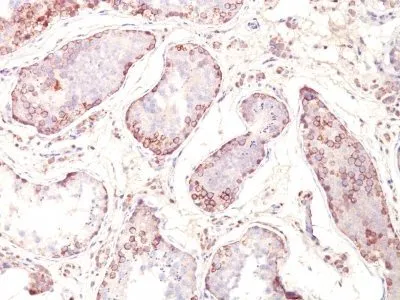

- Applications: IHC, FFPE (verified)

- Validated Applications: IHC, FFPE

- Positive Control: Melanoma cell lines. Melanomas, gliomas, neuroblastoma, non-small cell lung cancer, breast, gastric, colorectal, ovarian, and renal cell carcinomas.

- Additionnal Information: Higher concentration may be required for direct detection using primary antibody conjugates than for indirect detection with secondary antibody|Immunofluorescence: 1-2 ug/mL|Immunohistology formalin-fixed 0.5-1 ug/mL|Staining of formalin-fixed tissues requires boiling tissue sections in 10 mM citrate buffer, pH 6.0, for 10-20 min followed by cooling at RT for 20 minutes|Flow Cytometry 0.5-1 ug/million cells/0.1 mL|Optimal dilution for a specific application should be determined by user